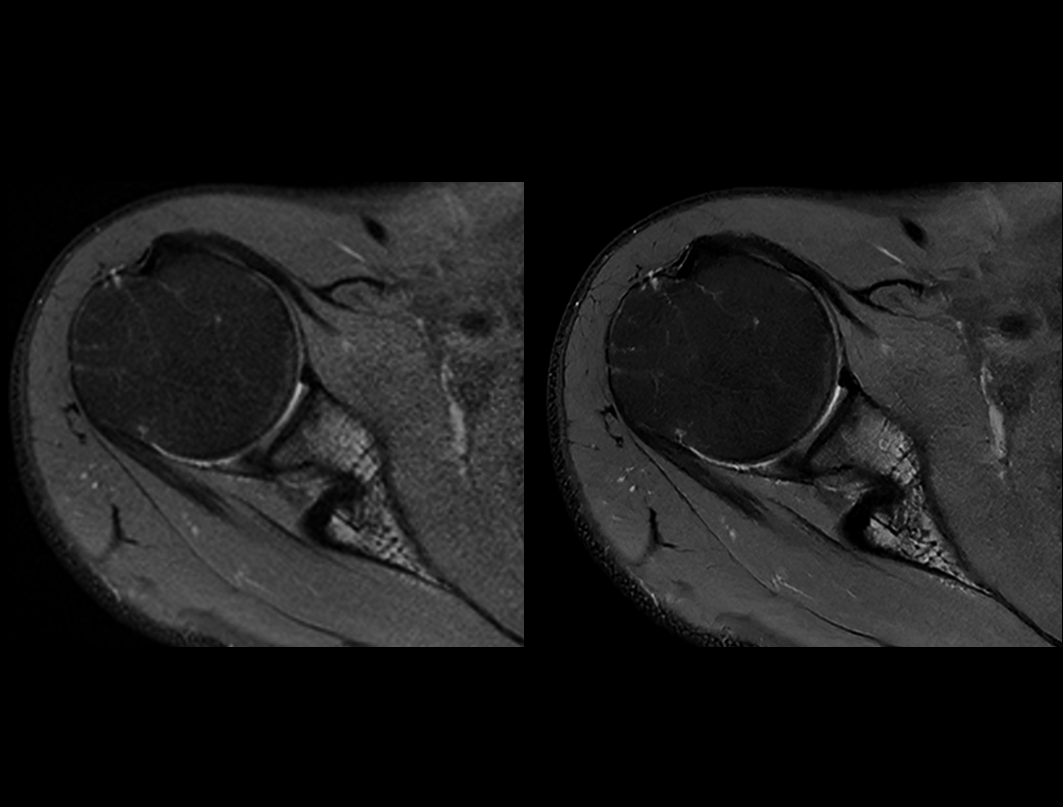

肩关节 PDW FS

常规成像 (2:56 min) vs. uAIFI DeepRecon™ (2:56 min)

0.29×0.29×3 mm3